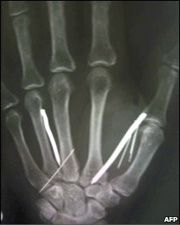

斯里蘭卡的醫生取出了一名曾在沙特當女佣的婦女體內的13根鐵釘和5根針。

X光透視片顯示,她的體內共有24枚釘子和針,目前尚未取出的對她的生命暫不構成威脅。

斯里蘭卡醫院的官員說,經過3個小時成功的手術,取出部分釘子,長釘子有5厘米長,目前艾裏雅瓦蒂正在康復。